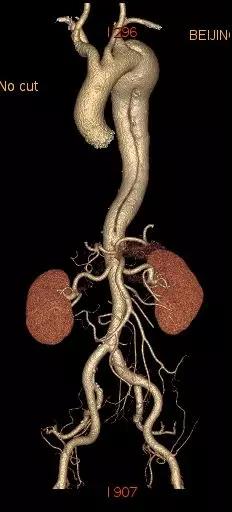

6月25日,中国医学科学院阜外医院向大会现场直播了一台采用先健新型主动脉支架系统进行的手术。手术由舒畅教授担任主要术者,接受手术的患者为一名65岁男性,入院后经CTA检查确诊为“慢性B型主动脉夹层”,夹层破口紧邻左锁骨下动脉,病变累及到两侧髂总动脉,主动脉真腔严重受压,假腔巨大,近端锚定区严重不足,病情十分危重。

经过测量和讨论,根据患者真腔受压严重、近端锚定区不足等特点,为了保留左锁骨下动脉,舒畅教授决定采用先健新型主动脉支架系统进行手术,该产品由Ankura™ Pro主动脉主体覆膜支架系统和Longuette™主动脉分支覆膜支架系统(即裙边支架)组成,其中Ankura ™ Pro 支架的径向支撑力比较大,适合慢性夹层病变,同时,其具有良好的柔顺性和多种锥度,对于急性和亚急性夹层患者也是非常好的选择。Longuette™裙边支架有较大的径向支撑力,保证支架在与主体支架配合使用时不被压塌;同时有极高的柔顺性,可顺应各种解剖形态的分支血管。其独特的设计对于累及弓上分支的主动脉夹层且病情紧急的患者具有明显优势。

术中通过DSA造影显示:主动脉夹层破口位于左锁骨下动脉近端,真腔压闭。舒畅教授通过左锁骨下动脉预置Longuette™裙边支架,释放 Ankura™ Pro主动脉主体覆膜支架,封堵破口后通过裙边支架显影点准确定位,释放裙边支架,凭借着舒畅教授精湛的手术操作和器械的优异性能,手术过程非常顺利,胸主动脉支架释放良好,患者的主动脉夹层破口封闭良好,左锁骨下动脉释放的裙边支架血流通畅,没有内漏发生。由于患者远端真腔较小,为了保证远端的血流,植入了一个cuff支架,造影显示远端真腔打开良好。